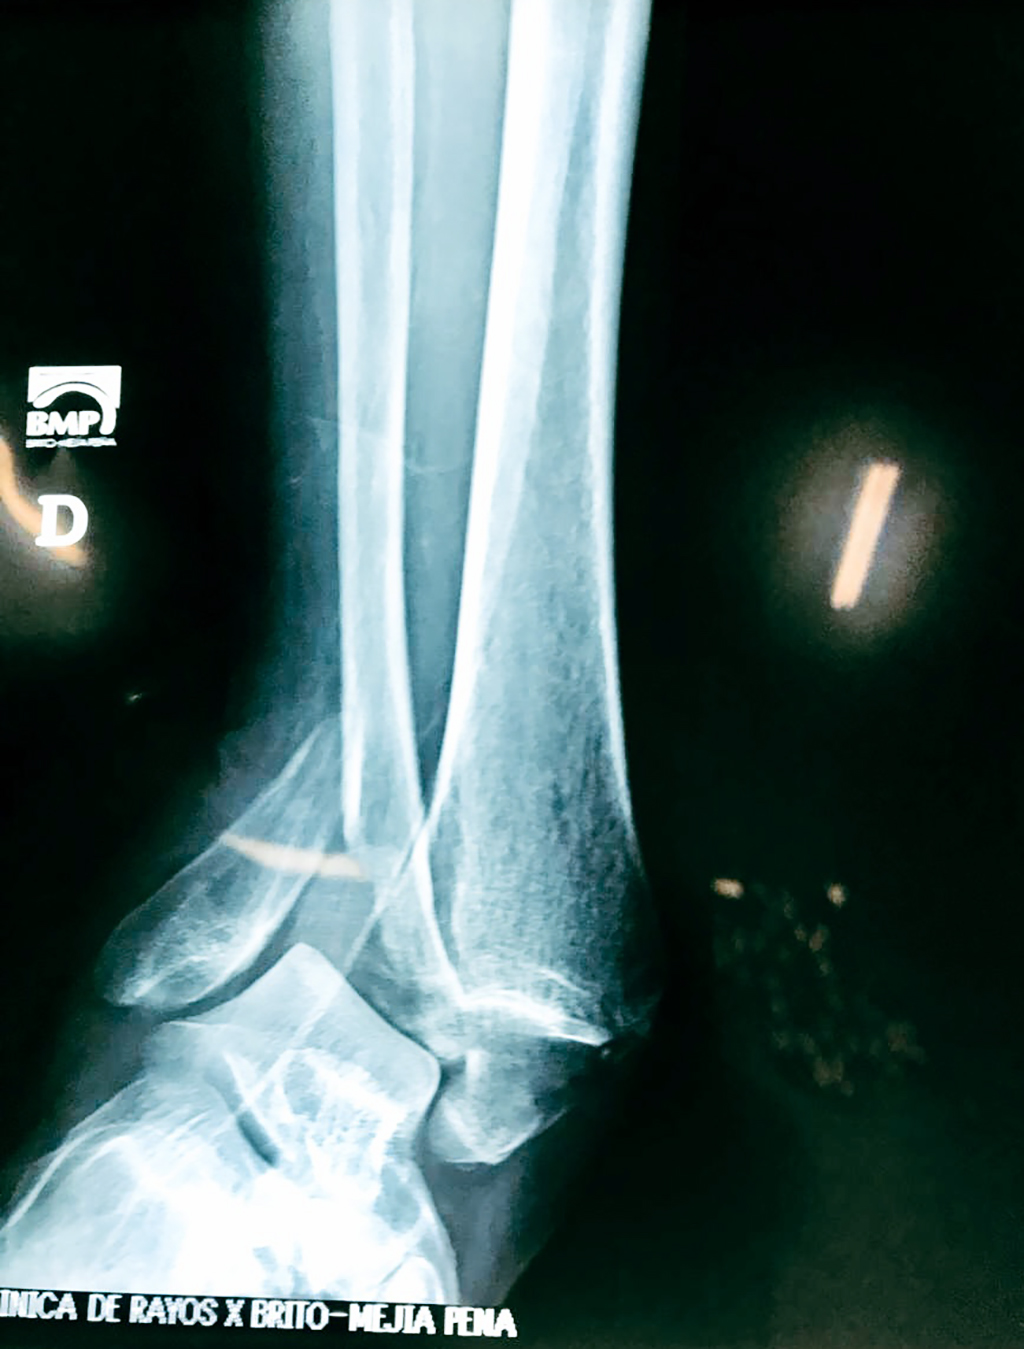

Una fractura de tobillo es la rotura de uno o más de los huesos del tobillo. Estas fracturas pueden ser:

Algunas fracturas de tobillo pueden requerir cirugía si:

- Los extremos de los huesos están desalineados entre sí (desplazados).

- La fractura se extiende hasta la articulación del tobillo (fractura intra-articular).

- Los tendones o ligamentos (tejidos que sujetan los músculos y los huesos entre sí) están rotos.

Cuando se necesita cirugía, es probable que esta implique el uso de clavijas de metal, tornillos o placas para sostener los huesos en su lugar mientras la fractura se consolida. Los elementos de soporte pueden ser temporales o permanentes.